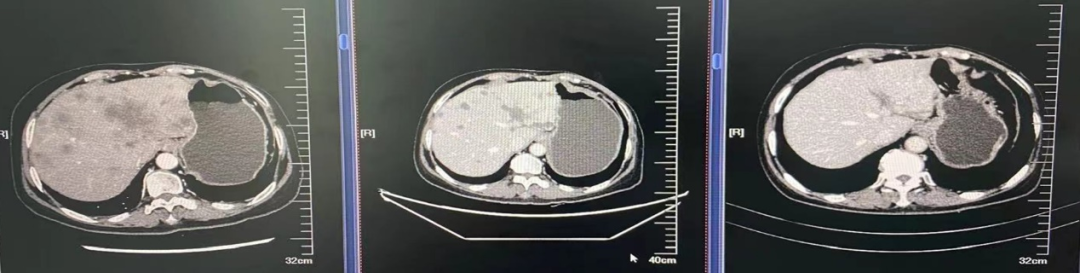

2021.04.05至荥阳市中医院查CT:1、左侧乳腺癌术后;2、双肺多发结节,转移可能,感染性病变待排;3、胸椎异常密度,转移可能;4、冠状动脉钙化;5、肝内多发低密度影。

2021.04.06至河南省肿瘤医院完善CT:双肺、肝、骨多发转移灶可能;ECT:全身多发骨质代谢异常,考虑多发骨转移。

(肝穿刺)腺癌浸润/转移,结合病史及免疫组化并见提示乳腺来源可能。DFI:21个月。